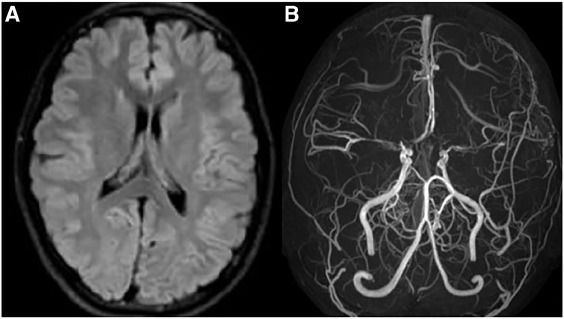

Moyamoya disease is characterized by progressive narrowing of vasculature of the brain. Vessels blockage consequently causes seizures and stroke. Moyamoya is a Japanese word which roughly translates into 'hazy' or 'puffy', the name suitable for puffy or cloudy appearance of blood vessels on angiogram. The patient usually presents with epilepsy, hemiparesis, transient ischemic attacks, and cognitive and memory impairment. The management involves medications and revascularization. Reference: https://www.hopkinsmedicine.org/health/conditions-and-diseases/moyamoya-disease#:~:text=Moyamoya%20disease%20is%20a%20chronic,%2C%20hemorrhagic%20stroke%2C%20and%20seizures. Image via: https://www.sciencedirect.com/science/article/pii/S1930043319300147